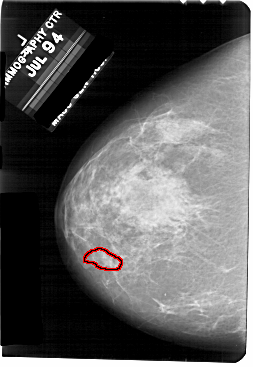

A_1707_1.RIGHT_CC

RIGHT_CC LINES 5491 PIXELS_PER_LINE 3106 BITS_PER_PIXEL 12 RESOLUTION 43.5 NON_OVERLAY

FILE: A_1707_1.LEFT_CC.OVERLAY

TOTAL_ABNORMALITIES 1

ABNORMALITY 1

LESION_TYPE CALCIFICATION TYPE PLEOMORPHIC DISTRIBUTION CLUSTERED

ASSESSMENT 4

SUBTLETY 1

PATHOLOGY BENIGN

TOTAL_OUTLINES 1

BOUNDARY